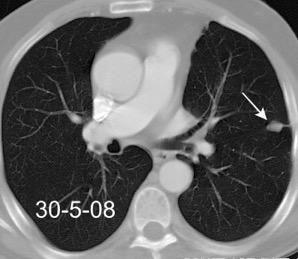

Tromboembolismo pulmonar.

Frecuencia del derrame:

Rx: 32%. TC: 47%

Unilateral. 85%

< 1/3 del hemitórax: 90%

Todos exudados

58% con eritrocitos

21% tabicación lo que causa demora en el diagnóstico

TEP. Empiema pleural. Atelectasia redonda